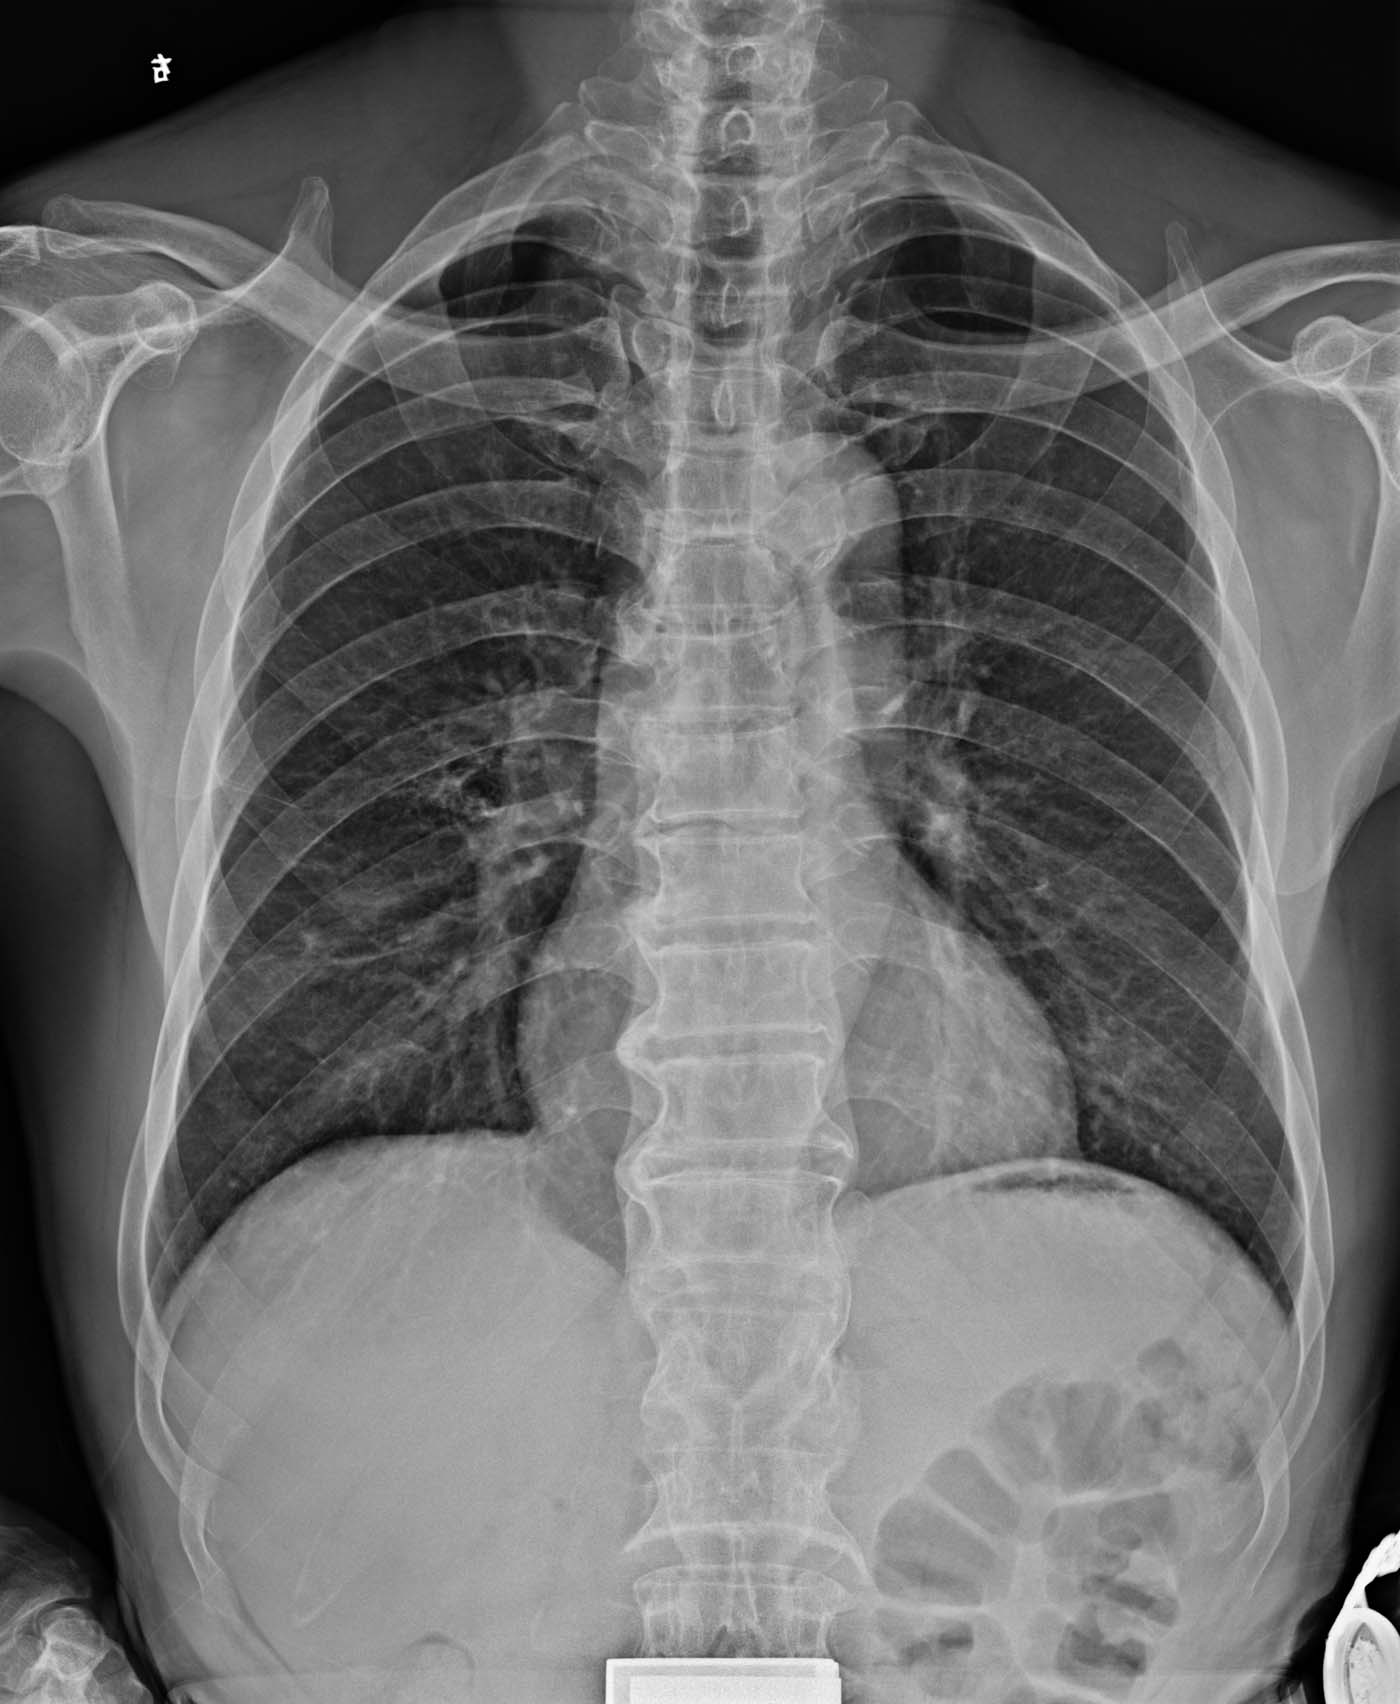

标题: X2088:右下肺背段囊性?空洞?

男,46岁,有咳嗽,无咯血,无发热。右下肺背段见一大小约1.5*1.5cm囊肿?还是空洞?,其内未见液平面,右下肺另见索条状密度增高影。

胸椎退变

右下肺有炎症吧,建议以ct

胸椎退行性骨关节病。建议ct检查除外肺部病变。

胸透发现右下肺囊状影或空洞影后进行摄片的。

右下肺看到条索状阴影,有没有空洞好像不怎么肯定,建议ct检查吧